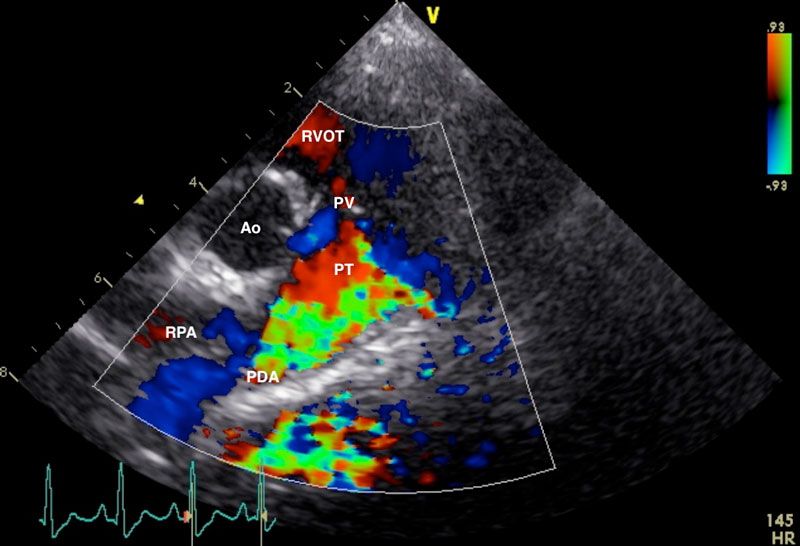

Figure 2: Right parasternal view of the aorta (Ao), right ventricular outflow tract (RVOT), pulmonary trunk (PT), and right pulmonary artery (RPA), showing a high velocity, turbulent, retrograde jet from the ductus ostium (DO) through the pulmonary trunk. Image courtesy of Dr Charlie Neill (University College Dublin).

Echocardiography: This is the gold standard for definitive diagnosis of PDA in dogs. It also allows exclusion of any concurrent cardiac defects (e.g., aortic stenosis, pulmonic stenosis, mitral dysplasia, persistent left cranial vena cava) (Van Israël et al, 2002; Van Israël et al, 2003; Saunders et al, 2014; McNamara et al. 2023). Typical findings may include left atrial and ventricular enlargement (Van Israël et al, 2002; Van Israël et al, 2003; Bureau et al, 2005; Manzoni et al, 2025), dilation of the main pulmonary artery, increased aortic ejection/outflow velocity, and turbulent flow in the pulmonary artery on doppler analysis (Figure 2). Acquired mitral regurgitation may also be identified (Van Israël et al, 2003; Bureau et al, 2005; McNamara et al, 2023; Manzoni et al, 2025).